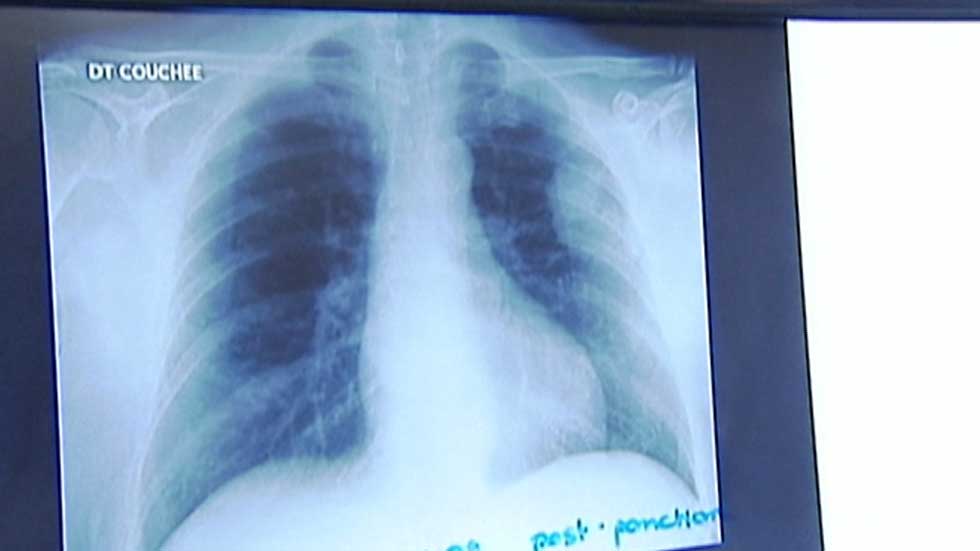

Dicen las estadísticas que cada vez hay más mujeres jóvenes con cáncer de pulmón. La mayoría son fumadoras pero otras no han fumado nunca. La comunidad científica busca una respuesta, en factores hormonales, ambientales o genéticos.